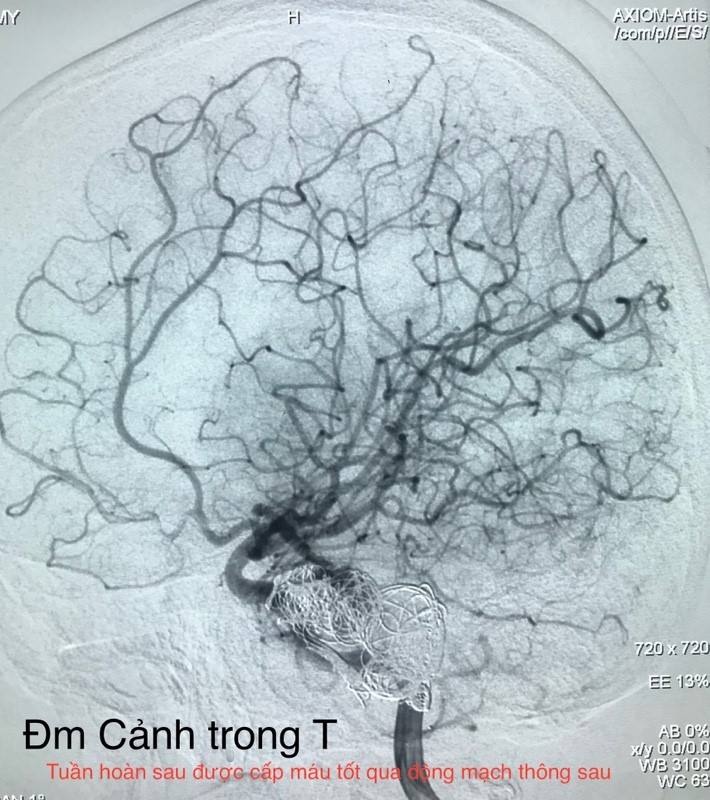

Tiếp theo đó, các bác sĩ lại luồn ống thông chọn lọc từng động mạch cảnh trong bên phải, bên trái để kiểm ra sự thông nối từ tuần hoàn não trước vào tuần hoàn não sau qua các động mạch thông sau.

![]() |

| Tuần hoàn sau được cấp máu tốt thông qua động mạch thông sau. |

Sau khi bơm thuốc cản quang, cây mạch máu não hiện ra, mạch máu từ tuần hoàn phía trước len lỏi xuống tuần hoàn phía sau, tới tận vị trí túi phình. Trong thời gian đó, bệnh nhân cũng không có triệu chứng gì, vẫn trả lời và thực hiện theo y lệnh được. Ê-kíp tiến hành hội chẩn lại lần nữa, quyết định đặt coil để tắc hoàn toàn động mạch đốt sống bên phải đoạn mang túi phình ấy. Lần lượt từng coil được đưa vào để lấp túi phình. Kết thúc quá trình can thiệp, bệnh nhân vẫn tỉnh táo, cử động, nói chuyện được.